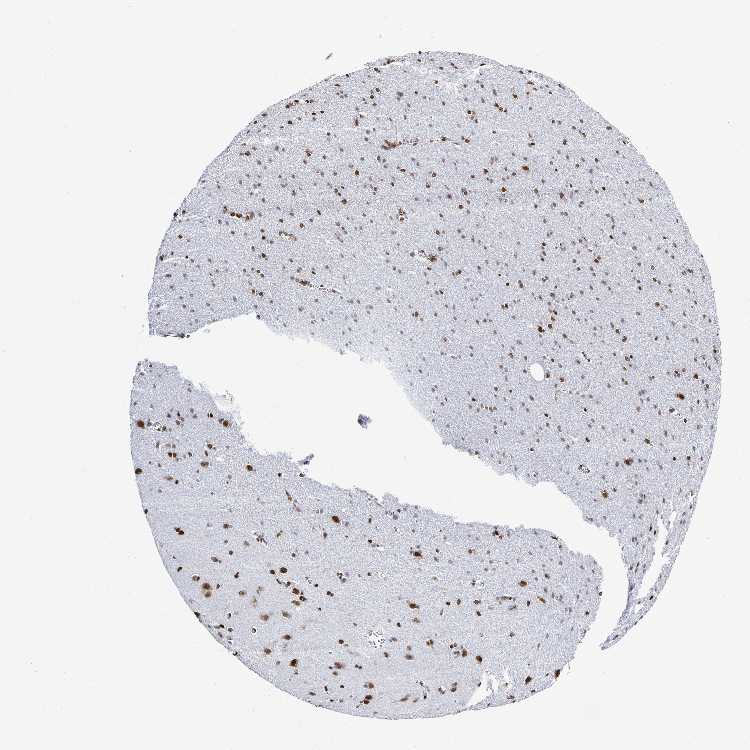

CEREBRAL CORTEX - Antibody stainingi

Antibody staining in the annotated cell types in the current human tissue is reported as not detected, low, medium, or high, based on conventional immunohistochemistry profiling in selected tissues. This score is based on the combination of the staining intensity and fraction of stained cells.

Each image is clickable and will lead to virtual microscopy that enables deeper exploration of all samples and also displays staining intensity scores, fraction scores and subcellular localization as well as patient and tissue information for each sample.

Antibody HPA059098

Endothelial cells Medium

Glial cells Medium

Neuronal cells High

Neuropil Not detected